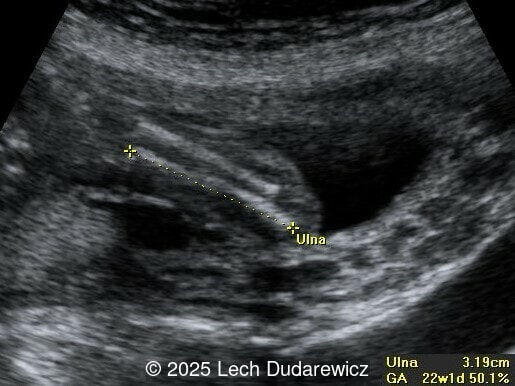

Ultrasound revealed a single live fetus with 46,XY karyotype. Biometric measurements demonstrated discrepancies with the femur and tibia length lagging significantly at 19 weeks and notable shortening and bowing of the femur, tibia, and fibula. The findings were consistent with skeletal dysplasia.

Prenatal ultrasound is a crucial tool for early diagnosis, enabling appropriate counseling and perinatal management of campomelic dysplasia. Key skeletal abnormalities include significant shortening and bowing of long bones, particularly the femur and tibia. In a study by Mansour et al, the lower extremities are primarily involved with minimal bowing of the humerus, ulna, and radius. Bowing often presents with associated angulation, giving rise to the term "campomelia," meaning bent limbs in Greek. Hypoplastic iliac bones and scapulae are hallmark features, while rib anomalies such as deformities or reduced number, typically 11 pairs, may also be observed. Additionally, the chest may be narrow and bell-shaped. Cervical spine abnormalities, including excessive lordosis or kyphosis, are often present and may contribute to postnatal respiratory complications. These findings are important for risk stratification and delivery planning.